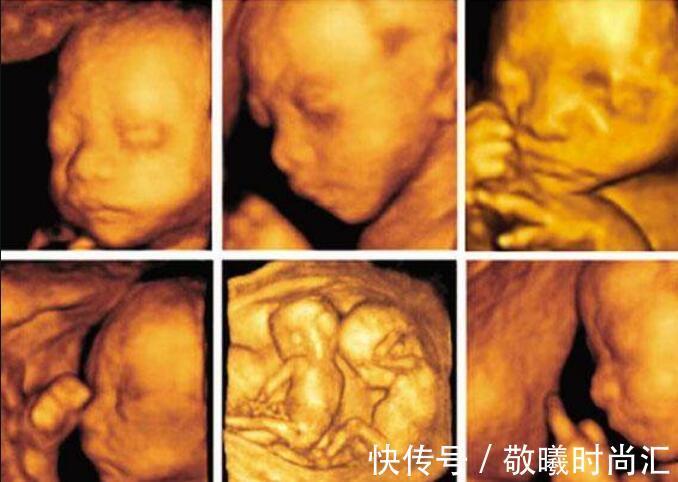

四维彩超属于超声检查的一种,除了一般得彩超功能外,还可以进行胎儿头面部立体成像,能够清晰地显示胎儿的眼、鼻、口、下颔等状态,能够协助医生直接对胎儿先天畸形进行诊断,包括表面畸形、内脏畸形和头面部畸形,同时还可以确定胎儿在子宫中的精确位置,实时观察胎儿动态的活动图像。不过四维彩超的主要任务是排查畸形,比如唇腭裂、无脑儿、脑积水、小头畸形、脊柱裂、脐部肠膨出、内脏外翻、肠道闭锁、肾积水、尿道梗阻、联体畸形、四心腔等等畸形,都可以检测出来,但是它并不是万能的,还有很多检测不出来的畸形,比如新生儿耳聋、白内障等等,就没有办法检测出来。而且检查时,对胎儿的配合度要求非常高,如果胎儿的姿势不太恰当,有些位置可能看不到,被忽略掉了;四维彩超也并不是百分百清晰可见的,有些地方可能会比较模糊,也会出现检查偏差。